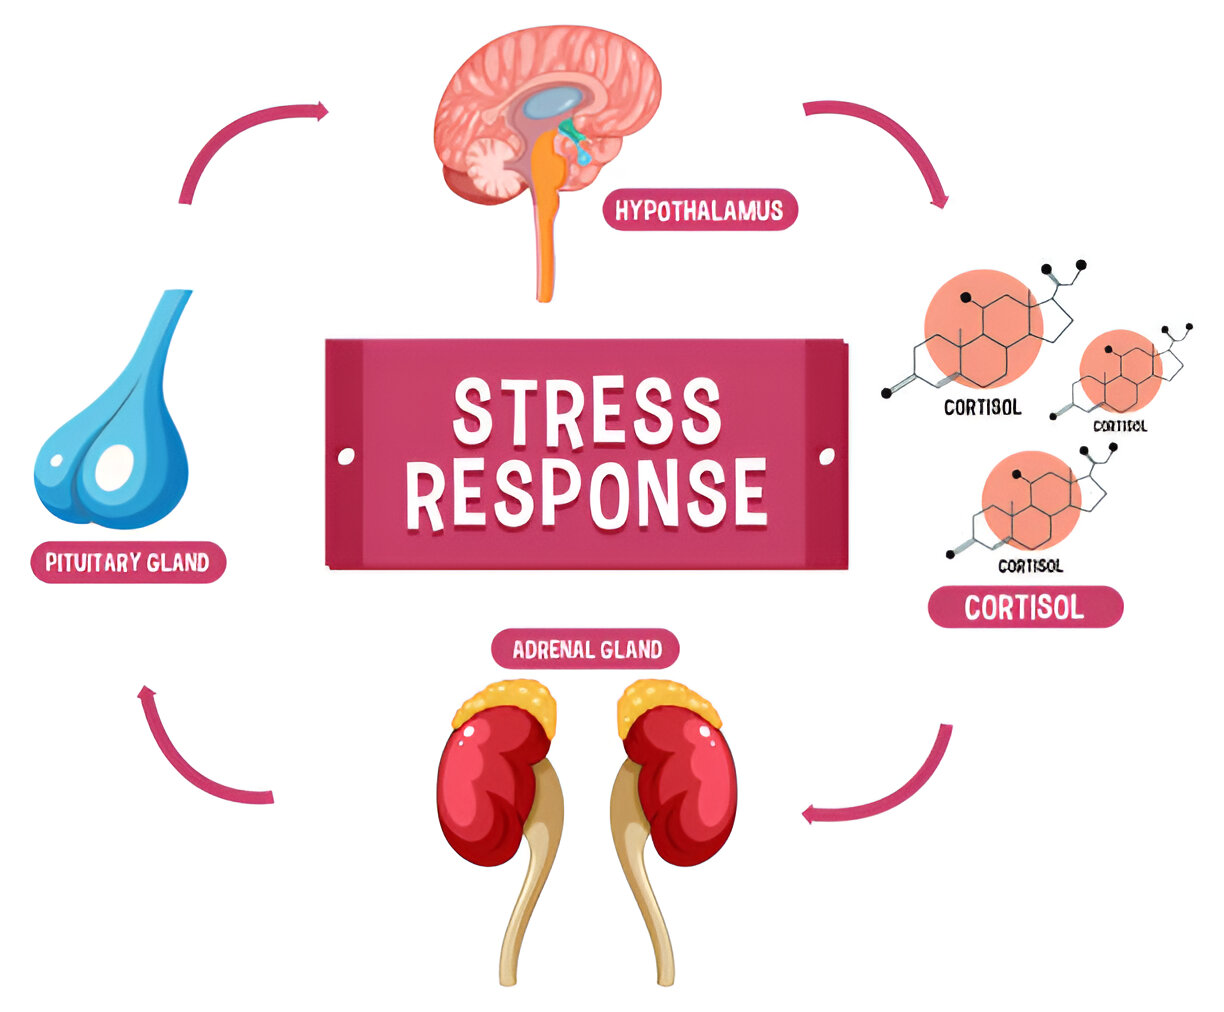

Adrenal glands ensure all hormones in your body are perfectly aligned. Adrenal glands are small, triangular shaped organs which are located above the kidneys and play a very crucial role in regulating the body’s stress response, blood pressure and metabolism.

In today’s fast-paced world, stress has become a common part of our daily lives. While occasional stress is a normal response to challenging situations, chronic or long-term stress can have serious consequences on your overall health, especially your hormonal balance.